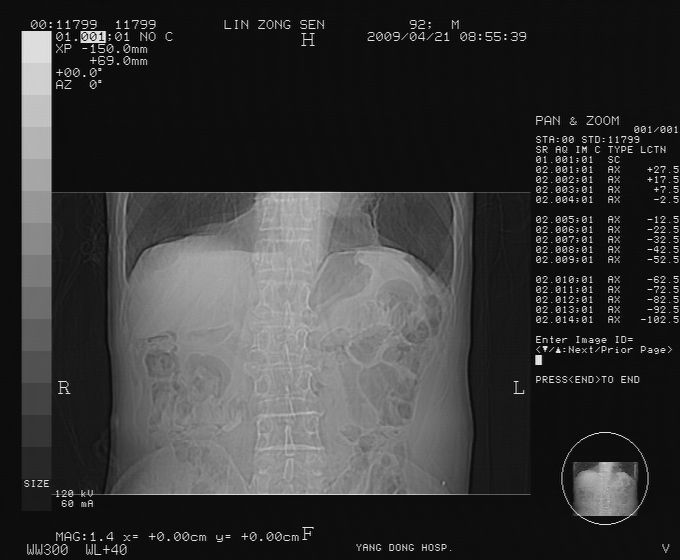

以下是引用卜一在2009-4-22 4:08:00的发言:[br]右肾积水伴输尿管上段积水!左侧肾多发囊肿!左侧腹壁软组织增厚,层次模糊,内密度较高—不排除血管瘤伴出血!